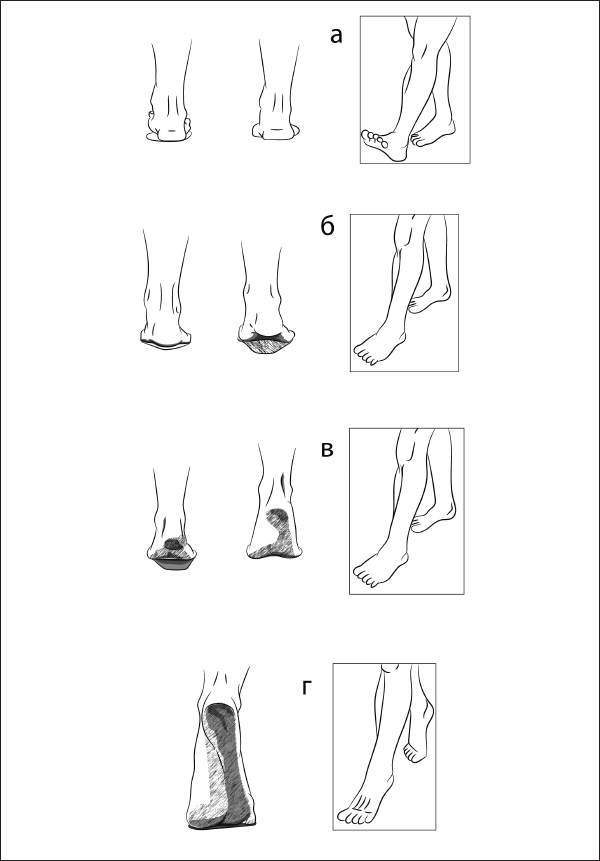

1. Фаза опоры: человек сгибает ногу, выносит ее вперед и опирается на пятку (рис. 28).

2. Фаза переката: перенос веса с пятки на пальцы, опираясь на нее – для вынесенной вперед ноги, и фаза переноса – для другой ноги, согнутой в коленном и тазобедренном суставах (рис. 29).

3. Фаза отталкивания: отталкивание от опоры в сочетании с разгибанием ноги (рис. 30, 31).

Рис. 28–31. Четыре фазы движения нижней конечности в паттерне шага. А – фаза опоры. Б – фаза переката. В – фаза опоры на пальцы. Г – фаза отталкивания.

Фаза переката стопыБиомеханика. Перекат стопы с пятки на носок производится по ее наружному краю с подъемом свода стопы. В движении участвуют передняя и задняя большеберцовая, а также малоберцовые мышцы.

Фаза отталкиванияБиомеханика. Производится отталкивание пальцами от опоры.